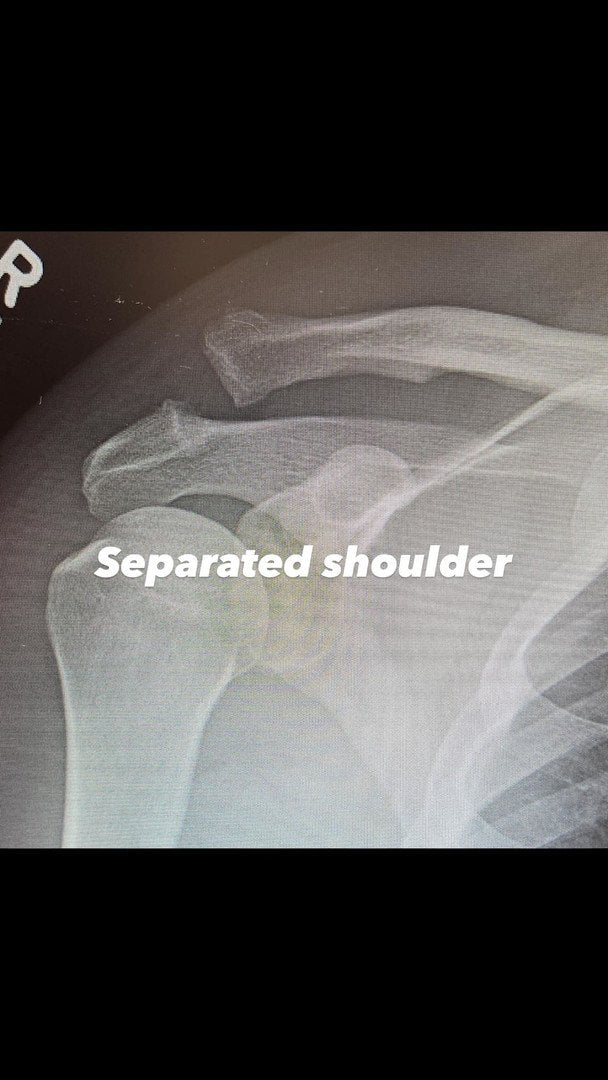

Ченнінг Татум уже показав рентгенівський знімок до та після хірургічного втручання. Актор не став розкривати, як саме дістав травму, лише запевнив, що впорається з усіма негараздами, хоча це й буде нелегко.

Плече Ченнінга Татума після операції / © instagram.com/channingtatum